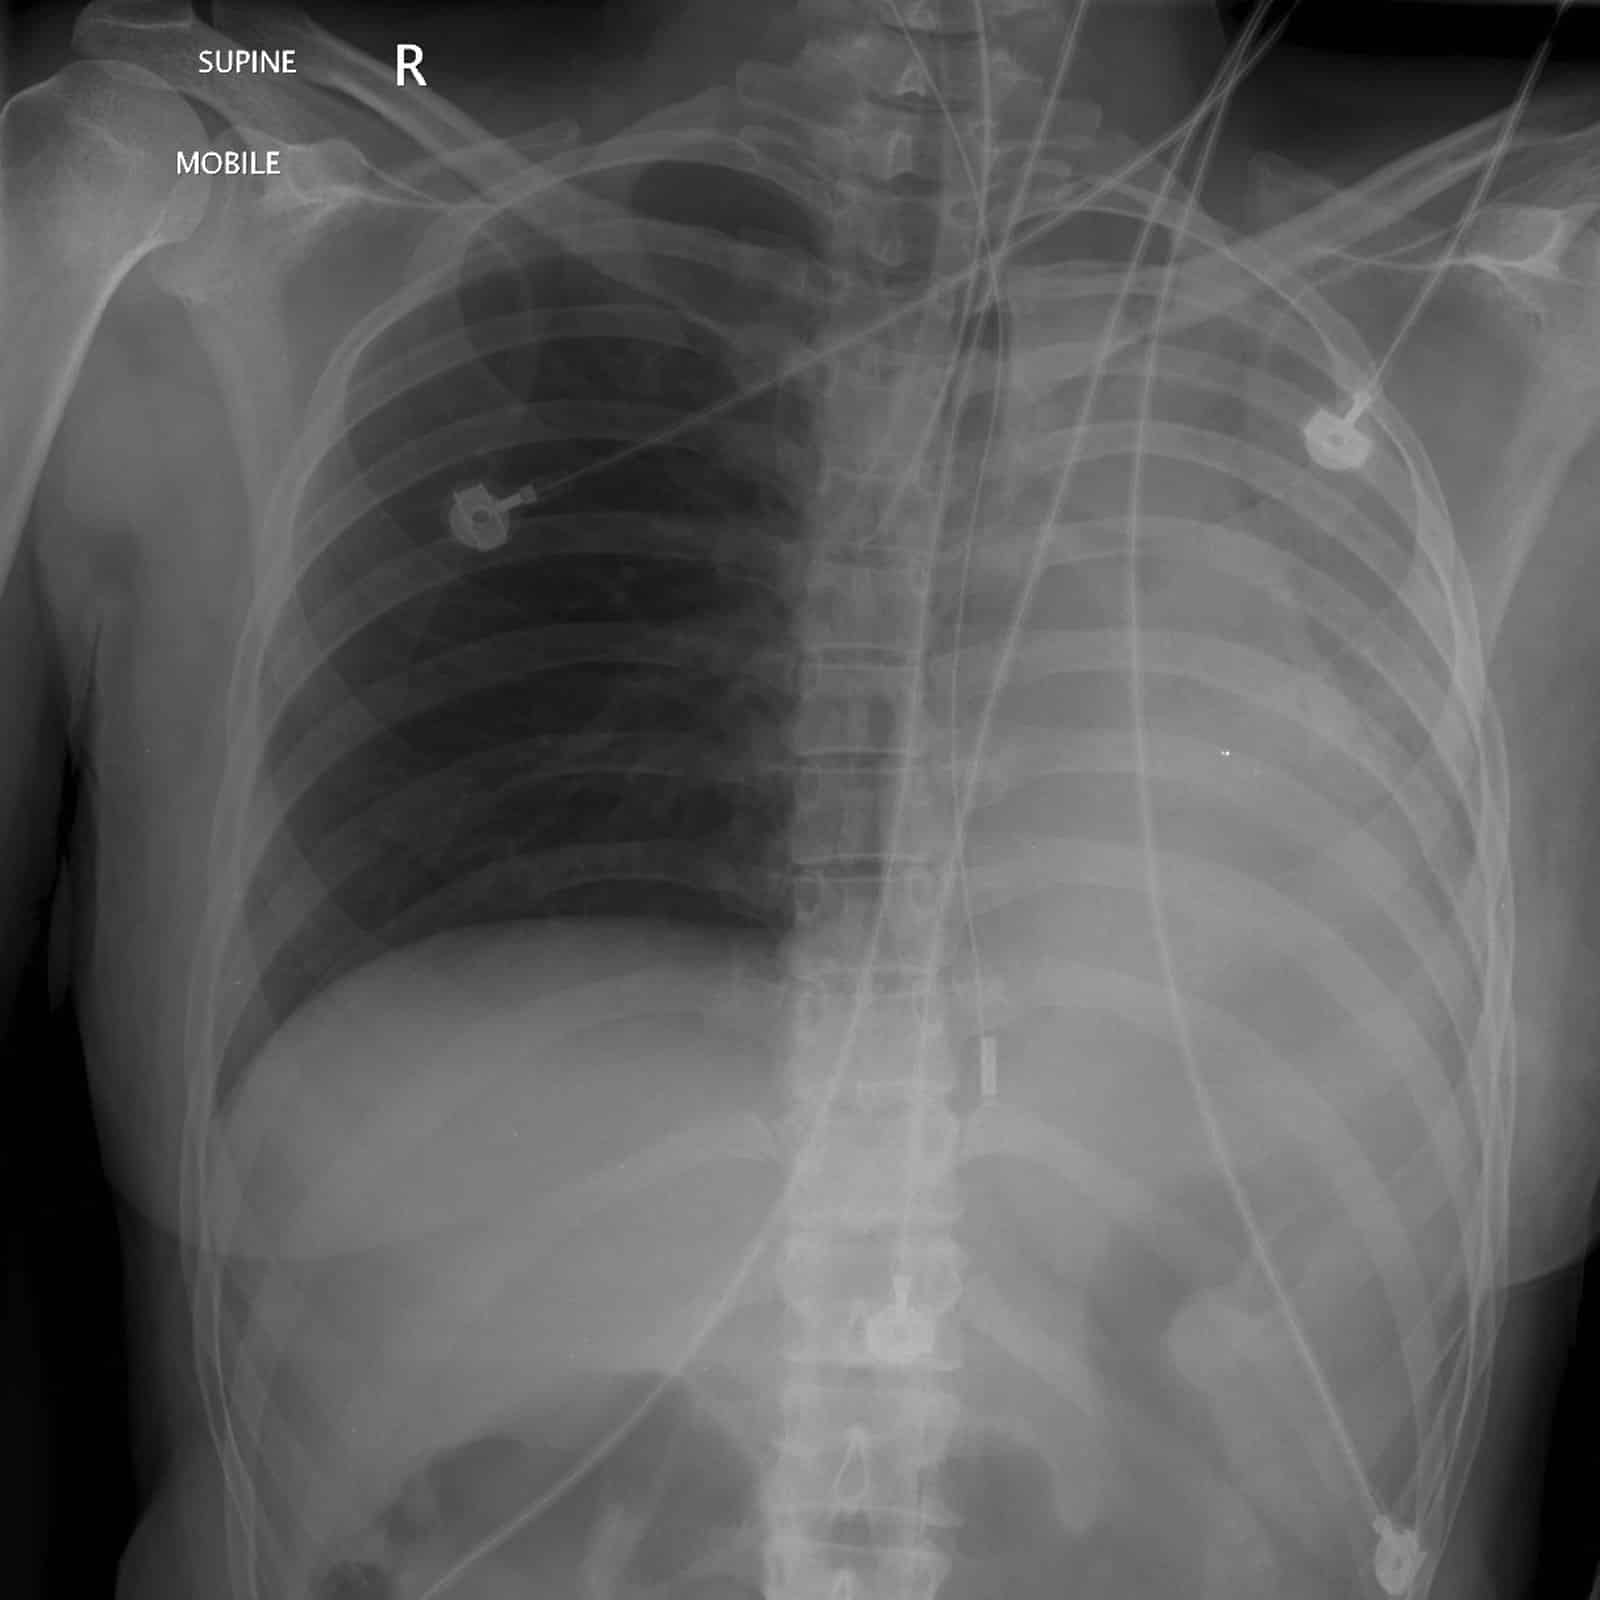

After performing these procedures, a chest X-ray can be used to confirm the ET tube positioned just above the carina. However, obtaining an X-ray to confirm placement must not interfere with the resuscitation process.

X-Ray view of ET tube properly placed above the carina

X-ray view of right mainstem intubation with white markings on the left chest indicating no air movement